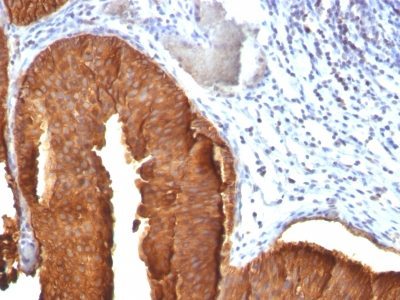

Recognizes a protein of 40 kDa, identified as cytokeratin-19 (CK19), which is expressed in sweat gland, mammary gland ductal and secretory cells, bile ducts, gastrointestinal tract, bladder urothelium, oral epithelia, esophagus, and ectocervical epithelium. Anti-CK19 reacts with a wide variety of epithelial malignancies including adenocarcinomas of the colon, stomach, pancreas, biliary tract, liver, and breast. Perhaps the most useful application is the identification of thyroid carcinoma of the papillary type, although 50%-60% of follicular carcinomas are also labeled. Anti-CK19 is a useful marker for detection of tumor cells in lymph nodes, peripheral blood, bone marrow and breast cancer.